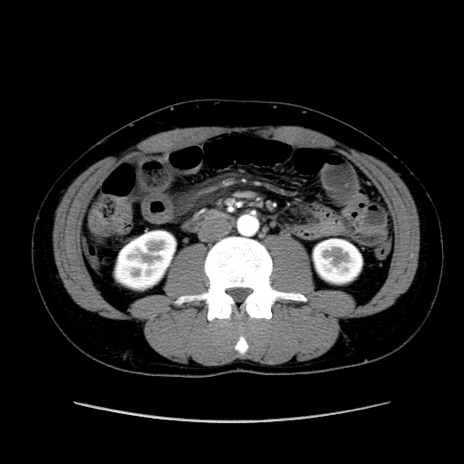

症例36(横断像)

【症例】20歳代 男性

【主訴】心窩部痛

【現病歴】今朝より上腹部痛あり。一旦軽快していたが再度出現したため救急要請。昨日夕に白身の魚を含む刺身を食べた。

【身体所見】BP 136/89mmHg、HR 74/min、BT 37.0℃、腹部:膨満、軟、心窩部に圧痛あり。反跳痛なし、筋性防御なし、腸雑音やや亢進あり。

【データ】WBC 17700、CRP 0.48